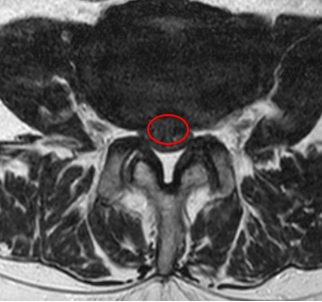

治療前

腰椎MRIで画像検査をしたところ、赤い枠で囲った箇所(L3/4)に椎間板ヘルニアができていました。